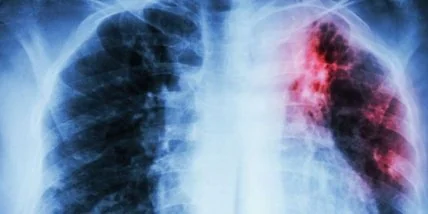

В Украине зарегистрирован новейший препарат деламанид, предназначенный для пациентов с расширенной резистентностью к противотуберкулезным препаратам.

Центр общественного здоровья Украины сообщил о регистрации впервые в стране новейшего препарата под названием деламанид, который предназначен для пациентов с расширенной резистентностью к противотуберкулезным препаратам.

Сообщается, что препарат критически важен для комплексного лечения туберкулеза с расширенной резистентностью. По данным 2015 года, результаты лечения пациентов с расширенной резистентностью к противотуберкулезным препаратам в Украине не превысили 36,7%.

ВОЗ сообщает, что Украина относится к странам, где уровень больных с мультирезистентным туберкулезом является одним из самых высоких в мире. Кроме того, Украина вошла в пятерку стран с самым высоким количеством зарегистрированных случаев ТБ с расширенной резистентностью - 1097 случаев в 2017 году.